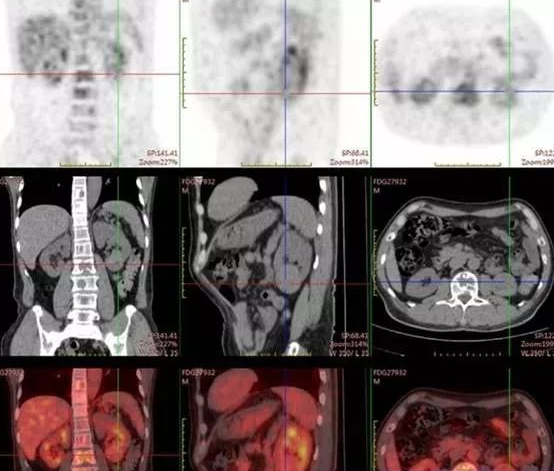

肾脏淋巴瘤PETCT检查案例

554x471 - 451KB - PNG